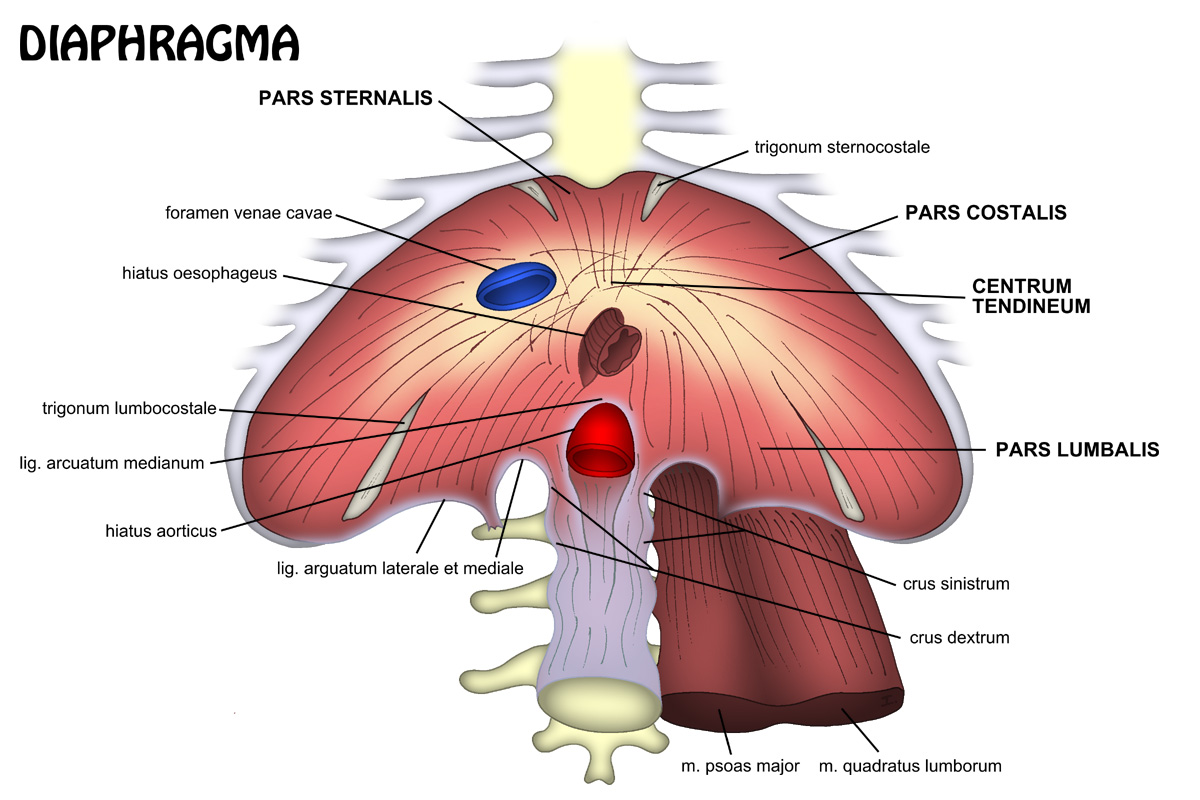

Анатомия диафрагмы и треугольника Бохдалека